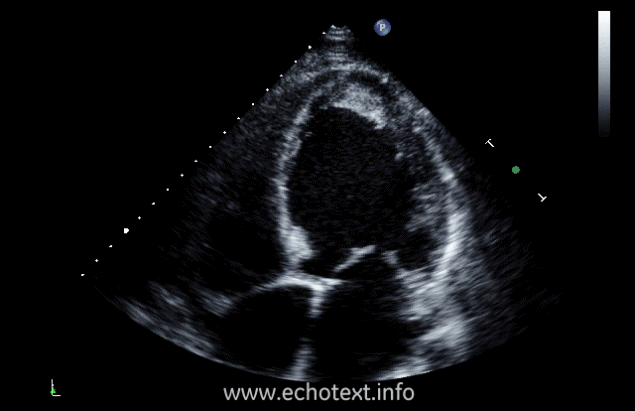

What cardiac pathology does this represent?

Aortic valve vegetations

Thickened /calcified aortic valve

Thrombus

Fibroelastoma